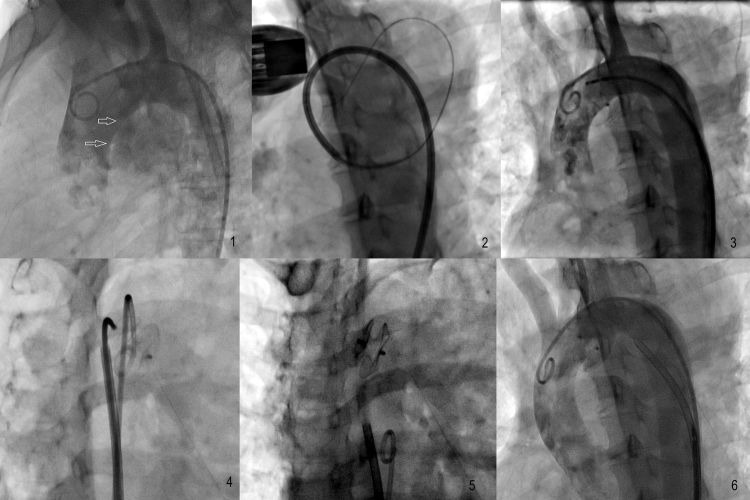

Fig. 2.

(1) Aortogram in left anterior oblique (LAO) 60 view shows communication (arrows) between aorta and pseudoaneurysm. (2) 7F long-curved sheath seen entering the aneurysm. (3) Aortogram in LAO view showing release of both discs nearly occluding the defect. (4) Aortogram in right anterior oblique (RAO) view confirming the separation of both discs on both sides. (5) Released device in RAO view. (6) Aortogram confirming sealing of communication with minimal foaming.

Under local anesthesia a 7 Fr bifemoral access was taken. The patient had received 325 mg of aspirin and 300 mg of clopidogrel prior to the procedure; 5000 units of unfractionated heparin were administered. A review angiography in the left anterior oblique and lateral view revealed a 9 mm opening within the undersurface of the aortic arch (Fig. 2, Video 1). Communication was entered using a 6F JR catheter with the help of a 300 cm Terumo wire [Japan]. A 7F long cocoon curved sheath was inserted into the aneurysm. Curved sheath was selected to overcome angulation of the arch of aorta (Fig. 2). A 10 mm Cocoon ASD device[Vascular Innovations Thailand] was inserted, and its position was checked with contralateral aortic pigtail shoot in both right anterior oblique and left anterior oblique views and with transthoracic echocardiography (Video 2). The device was released after confirmation of sealing of communication on echocardiography and angiography (Fig. 2, Video 3). A small leak remained on echocardiography and angiography post procedure. Her follow-up echocardiography showed 90% thrombosis of aneurysm on the third day with complete cessation of the leak. The patient showed gradual improvement in saturation over one week. She was discharged on the 7th day on dual antiplatelet therapy of aspirin and clopidogrel. On discharge, her oxygen saturation at rest was 94% at room air. Over a period of three months her dyspnea resolved completely, and only mild intensity dry cough persisted. Her echocardiograph at her three-month visit showed a gradient of 22 mm across the pulmonary artery. Her follow-up CT scan revealed thrombosed residual pseudoaneurysm with central colliquation and device in situ (Fig. 3). Echocardiography revealed reduction in main pulmonary artery compression. Gradient across main pulmonary artery had reduced to 16 mmHg. Symptomatically, the patient had no dyspnea and was NYHA Grade I/II.

Aortogram in left anterior oblique 60 degrees view shows communication between aorta and pseudoaneurysm.

Aortogram in right anterior oblique view shows separation of both discs and occlusion of the communication with minimal foaming of contrast.

Aortogram in left anterior oblique view after the release of device reveals almost complete occlusion of defect with minimal contrast foaming.